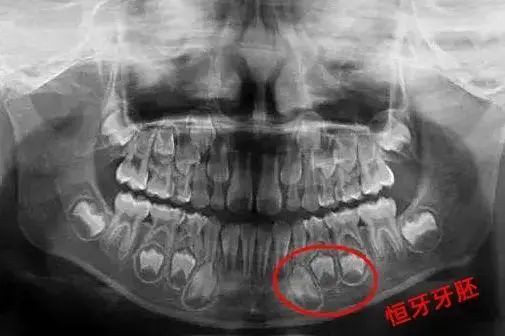

牙瘤是牙源性肿瘤。生长在颌骨内,主要是因牙胚组织发育异常形成的,形状不规则,数量有多有少。

正常情况下, 乳牙正常脱落后会萌出恒牙 。但如果乳牙因龋坏、根尖炎、外伤等因素造成的乳牙早失可能会影响恒牙牙胚发育,导致恒牙萌出异常,无法长出新牙。

因此,家长对于孩子的乳牙健康也要重视。 当乳牙出现龋齿、外伤等都应及时到正规的口腔医院进行就诊治疗 ,避免影响恒牙牙胚的健康发育。